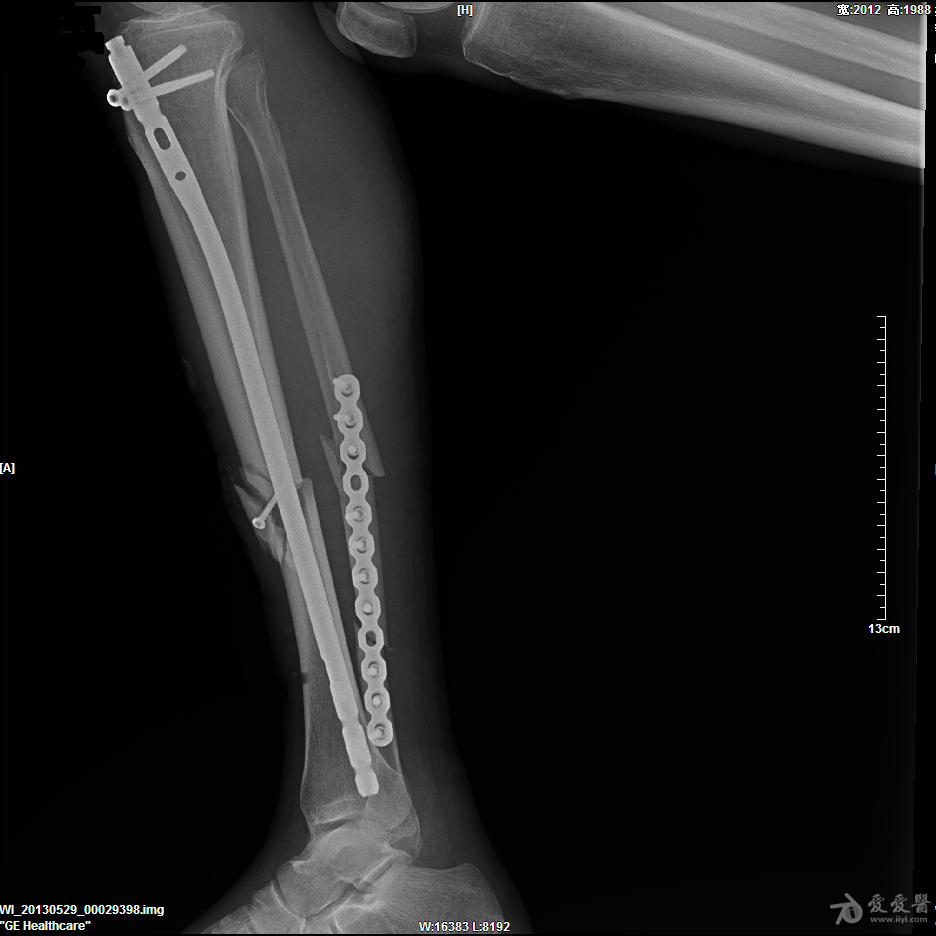

胫骨开放性骨折髓内针固定

57岁男性,骑摩托车摔伤,诊断1.右胫骨开放粉碎性骨折 2.腓骨粉碎性骨折 3.左锁骨粉碎性骨折(近、远端) 4.左肩胛骨粉碎性骨折 5.颅脑外伤。

入院后急诊清创缝合、右跟骨牵引,第9天,颅脑外伤稳定后行手术治疗。

这是术后片,术前片随后奉上。

胫骨髓内固定很好,远端的锁钉看不到了,不明白。至于胫骨的骨块上的螺钉和腓骨的板子,个人愚见纯属多余。

腓骨中断骨折没必要固定,而且固定不是很好。胫骨骨折断端的螺钉画蛇添足,影响愈合

楼主的手术观点可行,只是手术技巧还需进一步提高。1肩部的骨折应是一个浮肩损伤,片上隐约可以看到肩胛颈部的骨折,需要进行悬吊复合体完整性的恢复,或许肩胛骨进行固定效果会更理想。2腓骨骨折涉及到胫腓联合上8CM以内,所以需要固定,但胫腓骨的固定顺序错误,应先固定腓骨。如果术前或术中可以证实胫腓间韧带完整,腓骨的近端骨折可以不固定。3,aap髓钉提供立体的远端锁定,可以选择前后向先置钉。4像这样的带楔形骨块的简单骨折,易造成成骨不良,我更愿意选择双骨双钢板固定。